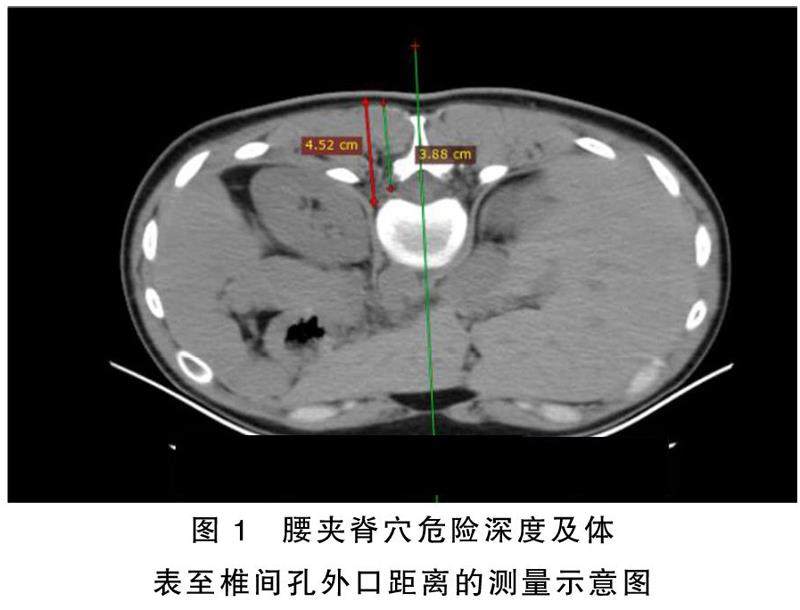

摘要目的:通过螺旋CT平扫技术测量腰夹脊穴针刺危险深度、安全深度及体表到椎间孔外口的距离。方法:选取2020年12月—2021年10月于山西省针灸医院放射科检查的体质指数(BMI)为(18.5~29.5)kg/㎡的成年志愿者54名作为研究对象,按性别分为男性组(27名)和女性组(27名),分别记录其年龄、体重(kg)、身高(cm)及BMI,在CT定位下,测量体表定位到腹腔的距离,即危险深度,根据公式安全深度=危险深度×75%获得安全深度;测量体表定位到椎间孔外口的距离。(剩余4666字)